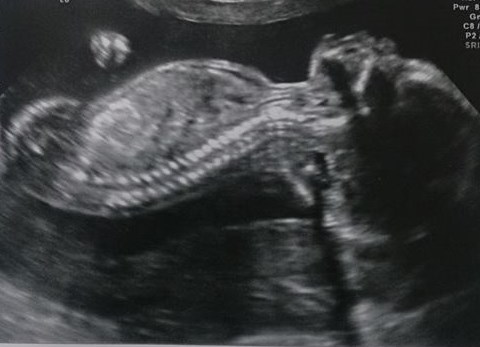

heres our little drama queen, causing bother already :)

wow that scan is so clear!!

Wow - that's an amazing scan; so clear. Fingers crossed for you.

missbrightside That scan is amazing, it sounds odd but her spine is beautiful!! I hope all is well for her!

missbrightside thats a fab scan picture and I really hope that the CF is just a false alarm.

cookie that doesn't sound odd at all, cos we were thinking along the same lines when we saw it, still can't believe how good a pic it is :) feel blessed to be carrying her xx

MissBrightside sending you positive vibes. It is an amazing picture!